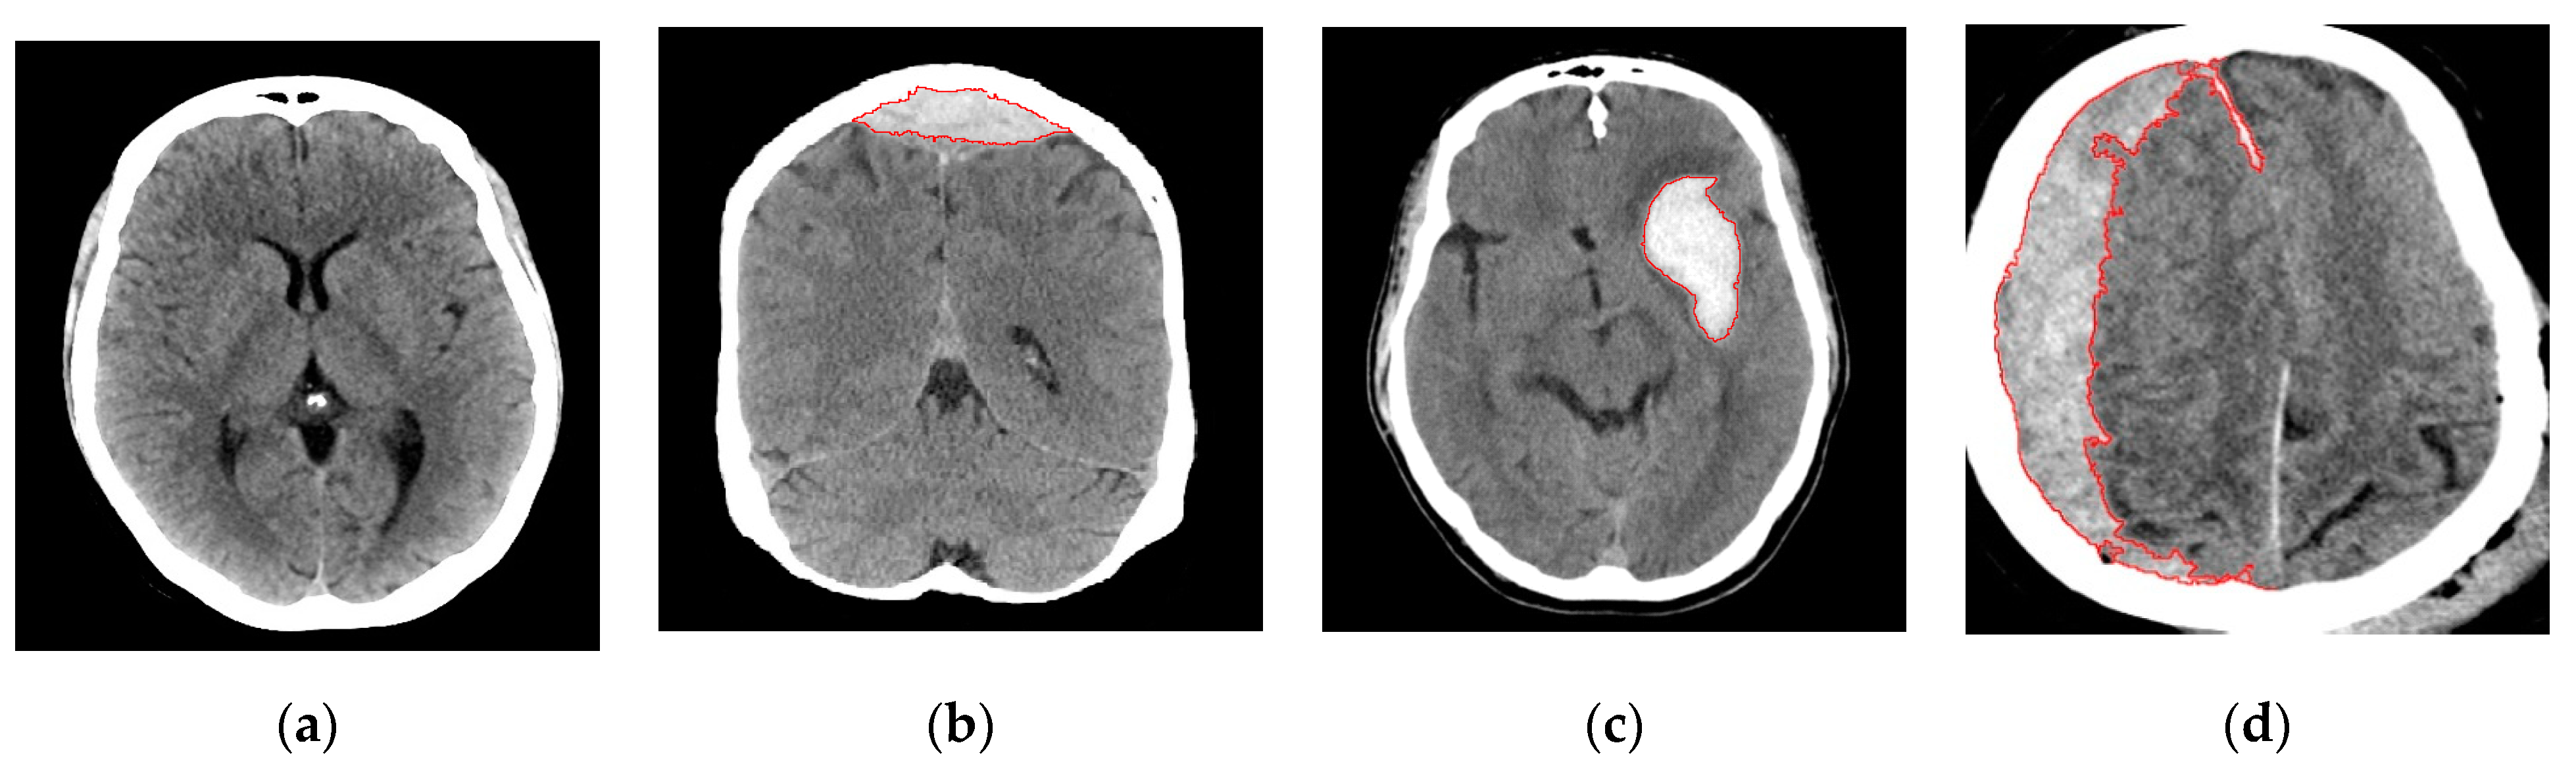

2.2.1. Image Segmentation

2.2.3. Region Growing